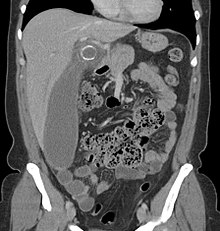

Where it is readily available, computed tomography (CT) has become frequently used, especially in people whose diagnosis is not obvious on history and physical examination. Concerns about radiation tend to limit use of CT in pregnant women and children, especially with the increasingly widespread usage of MRI.[49][50]

The accurate diagnosis of appendicitis is multi-tiered, with the size of the appendix having the strongest positive predictive value, while indirect features can either increase or decrease sensitivity and specificity. A size of over 6 mm is both 95% sensitive and specific for appendicitis.[51]

However, because the appendix can be filled with fecal material, causing intraluminal distention, this criterion has shown limited utility in more recent meta-analyses.[52] This is as opposed to ultrasound, in which the wall of the appendix can be more easily distinguished from intraluminal feces. In such scenarios, ancillary features such as increased wall enhancement as compared to adjacent bowel and inflammation of the surrounding fat, or fat stranding, can be supportive of the diagnosis. However, their absence does not preclude it. In severe cases with perforation, an adjacent phlegmon or abscess can be seen. Dense fluid layering in the pelvis can also result, related to either pus or enteric spillage. When patients are thin or younger, the relative absence of fat can make the appendix and surrounding fat stranding difficult to see.[52]